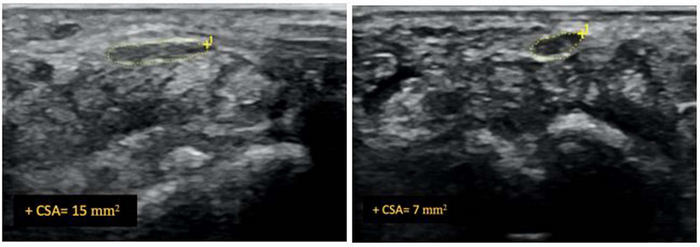

For this randomized control trial, Dr. Bose and colleagues enrolled a total of 63 patients suffering from carpal tunnel syndrome. Researchers used the Boston Carpal Tunnel Questionnaire (BCTQ), the Visual Analog of Pain (VAS), and cross-sectional area ultrasounds of the median nerve to assess patient pain and symptoms before and after the procedure. The 63 patients were divided into three groups. Group one received ultrasound-guided hydrodissection with just a saline injection. Group two received ultrasound-guided hydrodissection with an injection mixture of saline and corticosteroid. Group three received just an ultrasound-guided corticosteroid injection with no hydrodissection.

Additionally, ultrasounds showed a significant reduction of median nerve cross-sectional area in both hydrodissection groups. Group one showed a reduction of 43%, and group two showed 46%. Group three showed only an 11% reduction.